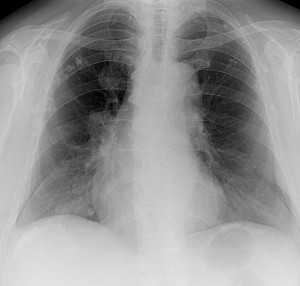

Метастазы в легких — фото рентгенограммы. Округлые тени — метастазы рака пищевода. Хорошо виден большой узел округлой формы вблизи переднего отрезка 2-го ребра. На снимке справа - циркулярное сужение пищевода за счет опухолевого утолщения его слизистой оболочки.

Как выглядят метастазы в легких на рентгене? Слева — узловые образования у пациента с раком яичка. Справа - метастазы рака яичников гематогенного характера с выраженным опухолевым лимфангиитом (обратите внимание на деформированный сетчатый, линейный характер легочного рисунка).

Гематогенные метастазы саркомы мягких тканей бедра на КТ (справа) и рентгенограмме (слева).

Обратите внимание на увеличение и нарушение структуры корня правого легкого. Это центральный рак. Кроме того, выявлены очаговые тени в обоих легочных полях (гематогенное распространение), а также «лучи», идущие радиально от опухоли корня (лимфогенное распространение).